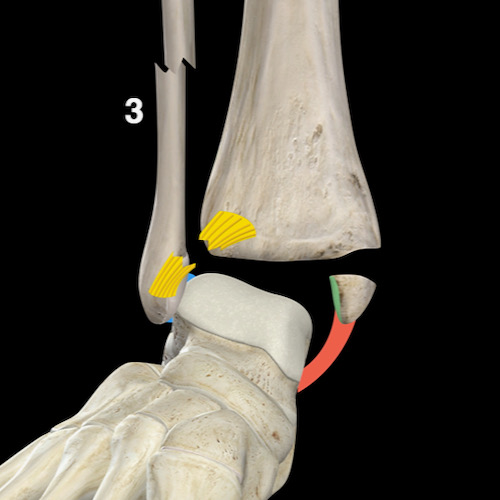

Bước 3 – Liệu đây có phải là Weber C / PER không?

Khi X-quang cổ chân không cho thấy gãy xương rõ ràng như Weber A hoặc B, câu hỏi đặt ra là: liệu đây có phải là gãy xương Weber C không?

Vì đường gãy xương mác trong Weber C thường không hiển thị trên X-quang cổ chân, đây có thể là một câu hỏi khó trả lời.

Chúng ta sẽ phải tìm kiếm các dấu hiệu bổ sung để dẫn đến câu trả lời đúng và giúp chúng ta quyết định có cần chụp thêm hình ảnh hay không.

Vì đường gãy xương mác đã ở giai đoạn 3, chúng ta muốn tìm kiếm:

- Giai đoạn 1 là tổn thương phía trong (medial), nơi mọi thứ bắt đầu. Bất kỳ cơn đau hoặc phù nề phần mềm ở phía trong đều có thể là dấu hiệu đầu tiên cho thấy chúng ta đang đối mặt với gãy xương Weber C.

- Giai đoạn 2 là tổn thương khớp chày mác xa (syndesmosis) phía trước, thường không nhìn thấy được, trừ khi có gãy xương Tillaux.

- Giai đoạn 4 là tổn thương khớp chày mác xa phía sau, đôi khi không thể nhìn thấy, nhưng sẽ bị nghi ngờ nếu có sự giãn rộng của khớp cổ chân hoặc khi có mảnh avulsion của mắt cá sau (malleolus tertius) như được thấy trong hình minh họa.

Đôi khi chúng ta may mắn vì đường gãy xương mác có thể nhìn thấy trên X-quang cổ chân.

Khi đó chúng ta biết mình đang đối mặt với gãy xương Weber C giai đoạn 3 không ổn định.

Trong trường hợp này, có sự giãn rộng khoang sáng phía trong (medial clear space) giữa mắt cá trong và xương sên, cho thấy đứt dây chằng bên trong (giai đoạn 1).

Chúng ta phải giả định rằng cũng có đứt khớp chày mác xa phía trước (giai đoạn 2).

Ngoài ra cũng có thể có tổn thương giai đoạn 4 ở khớp chày mác xa phía sau.

Tuy nhiên, trong nhiều trường hợp, đường gãy xương mác nằm ở vị trí cao hơn và chúng ta cần chụp thêm X-quang để tìm đường gãy.

Nhiệm vụ của chúng ta với tư cách là bác sĩ chẩn đoán hình ảnh là tìm kiếm các dấu hiệu gợi ý trên X-quang cổ chân để dẫn đến các đường gãy xương mác cao này, và thuật toán sẽ hỗ trợ chúng ta trong việc đó.